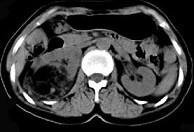

问题 女,53岁,右侧轻度腰背酸痛,行CT检查,如图所示,可能的诊断为()

选项 A.右肾上腺髓样脂肪瘤 B.右肾上腺腺瘤 C.右肾上腺嗜铬细胞瘤 D.右腹膜后脂肪瘤 E.右肾血管平滑肌脂肪瘤

答案 A